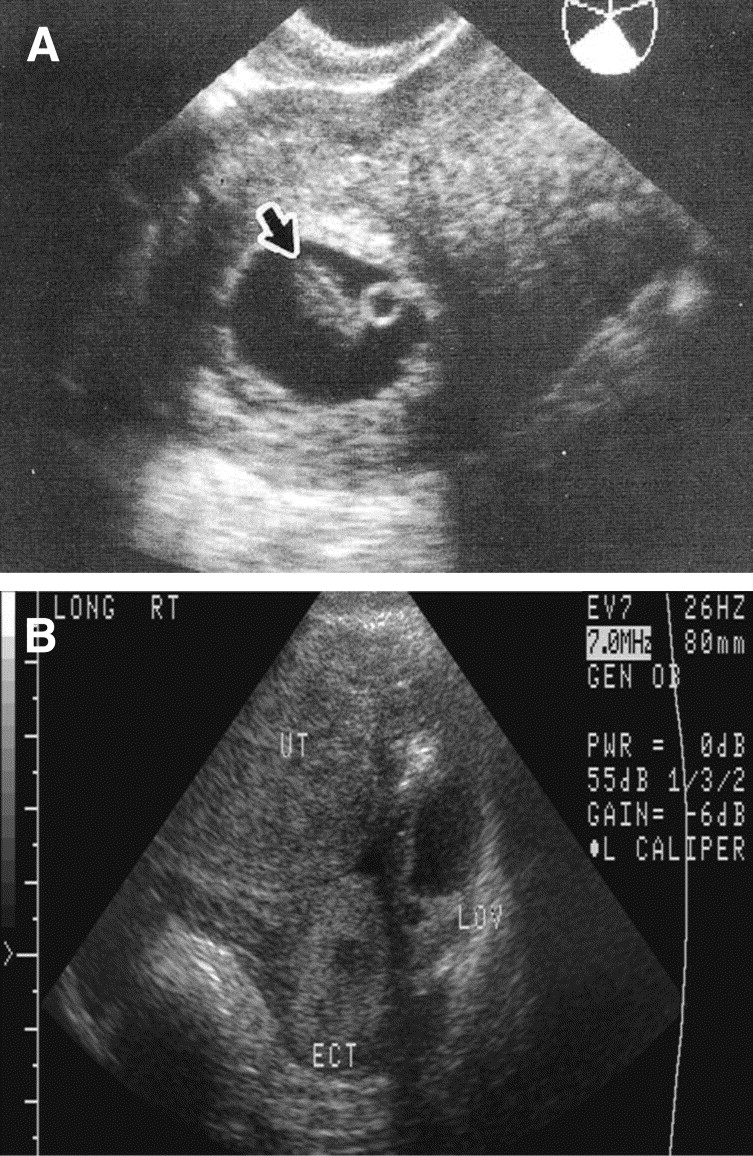

عکس سونوگرافی بارداری خارج از رحم